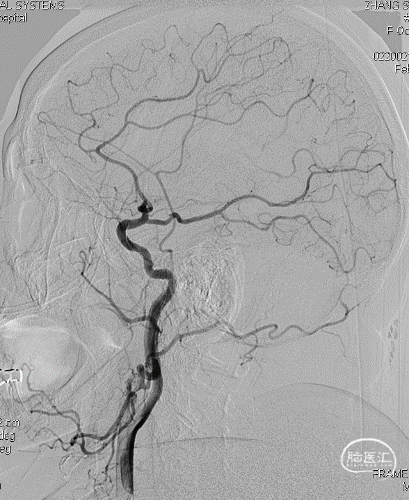

局麻,右股动脉入路置8F短鞘,导管导丝技术将8F MPA置于右C1末端,造影确认右M1急性闭塞,侧支代偿差。

以Transend-14导丝 + Headway21导管到达M1中段,Sofia Plus顺畅到位(M1中段),ADATP技术抽吸取栓,一次成功取通,前向血流TICI 3级,无栓子逃逸及原位狭窄,穿刺至开通时间仅用时9min。

DSA造影见右侧大脑中动脉M1中段以远闭塞,ACA向MCA区域仅少量代偿。Sofia Plus在Headway21导管及Transend导丝引导下,很顺畅通过虹吸段等部位,到达M1中段。

采用ADAPT技术,血流快速复通;最右图为Sofia Plus导管前端及取出血栓。